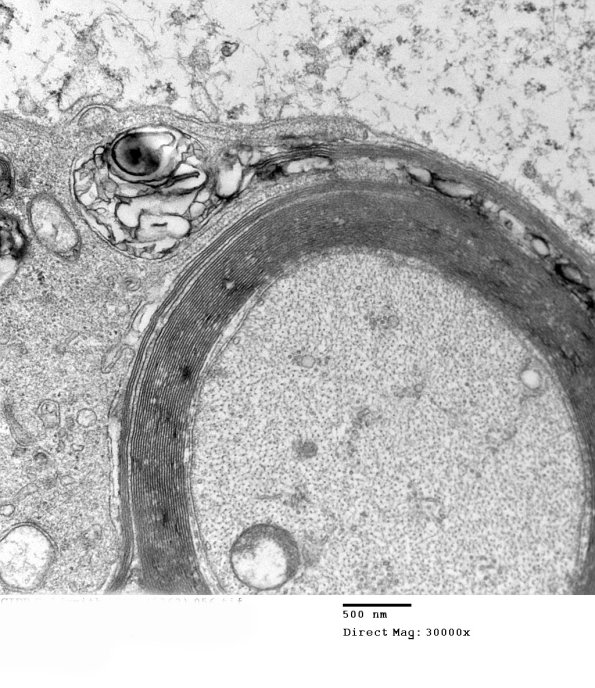

1D8B,C Again notice the peeling of otherwise normal myelin. (electron micrographs)